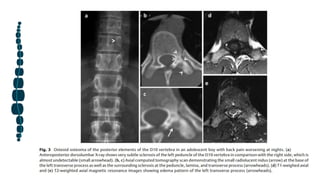

Los osteoblastomas comúnmente afectan la columna vertebral (30-40% de los casos) y con mayor frecuencia

se originan en los elementos posteriores (85% de las lesiones) con 42% extendiéndose en el cuerpo

vertebral. Pueden presentarse con dolor, parestesias, paraparesia o incluso paraplejía.

Los osteoblastomas espinales pueden presentarse con apariencias radiológicas variables. El

primer patrón es similar al osteoides osteoide y está compuesto por un nido radiotransparente y

circundante esclerosis, pero tienen> 2 cm de diámetro.

La apariencia más común del osteoblastoma espinal es una expansión lesión con un borde

esclerótico prominente y múltiples pequeños calcificaciones. El tipo más agresivo demuestra un

patrón expansible con calcificaciones de la matriz, destrucción ósea y extensión paravertebral que

imita un aneurismático quiste óseo o metástasis ósea

El examen diagnóstico de elección es la TC; sin embargo, MRI describe la afectación de los tejidos

blandos circundantes a una mejor grado. La TC muestra el nido, el multifocal (a diferencia de

central en los osteomas osteoides) calcificación de la matriz, la esclerótica margen, la

remodelación ósea expansiva, o un hueso óseo delgado concha alrededor de sus márgenes.